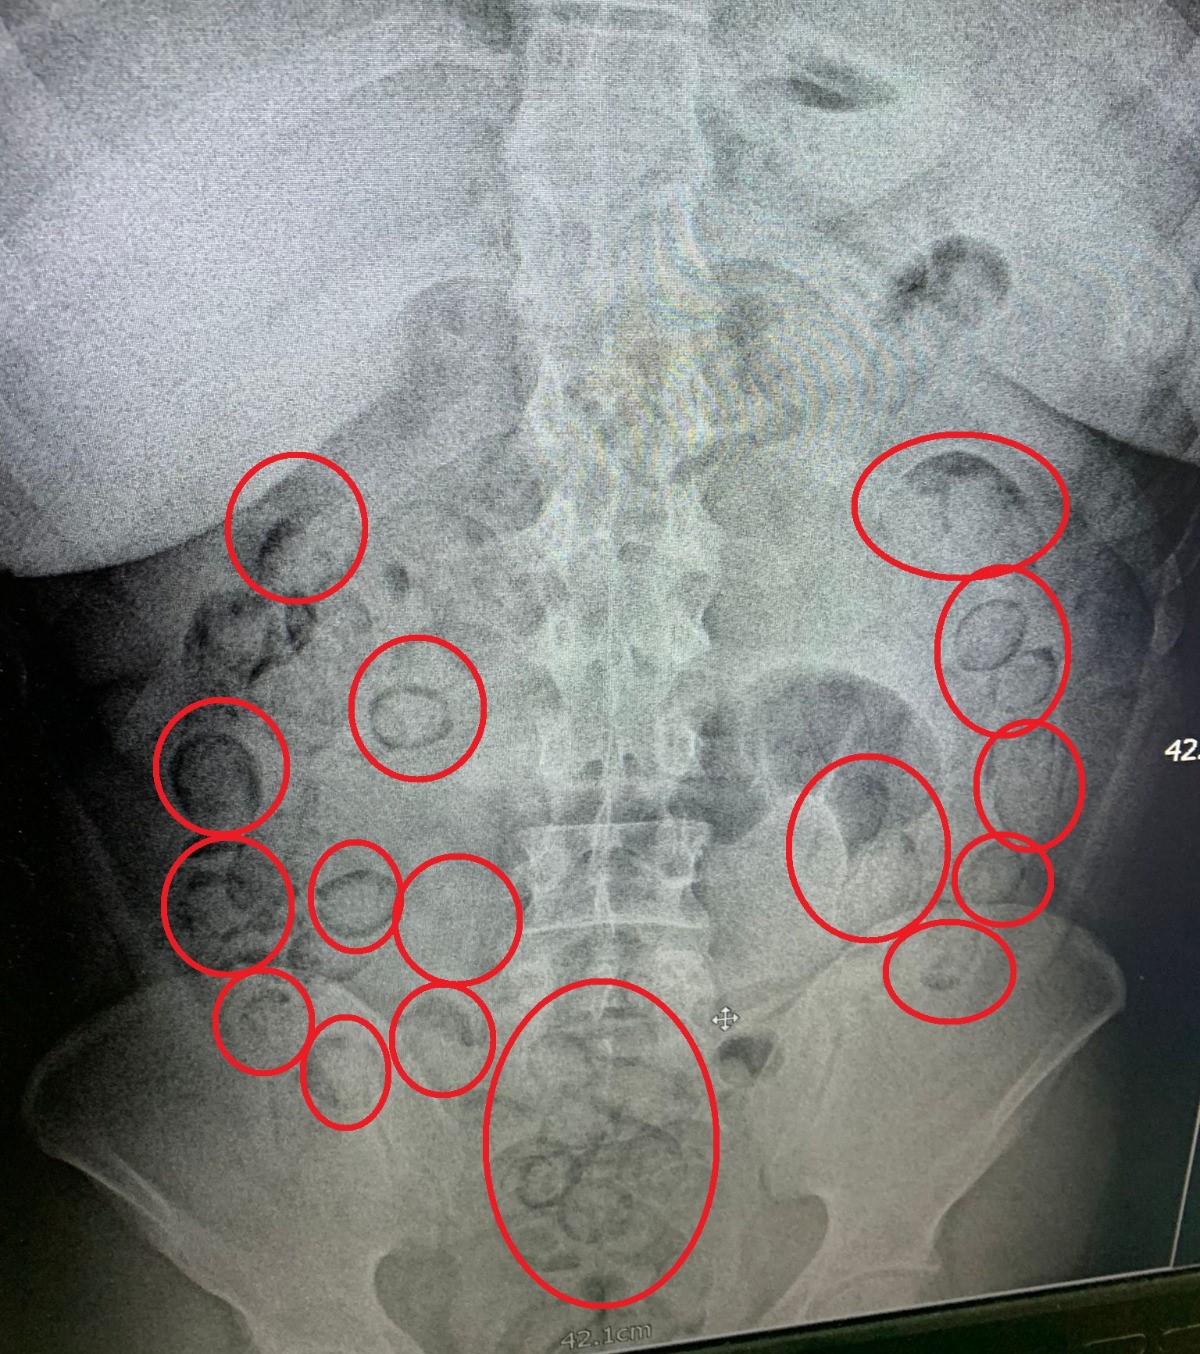

Aksaray’da narkotik ekiplerince düzenlenen operasyonda yakalanan İran uyruklu uyuşturucu tacirinin midesinde 101 parça halinde 433 gram metamfetamin maddesi ele geçirildi.

Edinilen bilgiye göre, İl Emniyet Müdürlüğü Narkotik Suçlarla Mücadele Şubesi ekipleri, yaptığı analiz çalışmasında İran’ın başkenti Tahran’dan ülkeye uyuşturucu getirileceği bilgisine ulaştı. Bunun üzerine Aksaray Cumhuriyet Başsavcılığı koordinesinde harekete geçen ekipler kimliği belirlenen A.M. (20) isimli İran uyruklu şahsı teknik ve fiziki takibe aldı. Narkotik ekipleri şahsın uçakla Ankara’ya geleceği bilgisi üzerine harekete geçti. Ekipler Ankara’da uçaktan inen şahsı takibe aldı. Ankara’dan otobüse binen uyuşturucu taciri otobüsle Aksaray’a geldi. Aksaray’da E-90 karayolunda şahsın otobüsten inmesi üzerine operasyon için düğmeye basan ekipler şahsı kıskıvrak yakalayarak gözaltına aldı. Yapılan kontrollerin ardından uyuşturucuları midesine yutarak muhafaza ettiği düşünülen şahıs Aksaray Eğitim ve Araştırma Hastanesine götürülerek iç beden muayenesinden geçirildi. Tomografisi çekilen şahsın midesinde vücut dışı parçaların olduğu tespit edildi. Hastanede doktor kontrolünde ilaç içirilen İran uyruklu tacir bir süre sonra polis kontrolünde büyük tuvaletini yaparken, şahsın midesinden prezervatife sarılmış 101 küçük paket çıktı. Paketlerin içini açan polis, toplam 433 gram metamfetamin maddesi ele geçirdi. Uyuşturucu maddelere el konulurken, uyuşturucu taciri emniyetteki işlemlerinin ardından sevk edildiği adli makamlarca tutuklanarak cezaevine gönderildi.